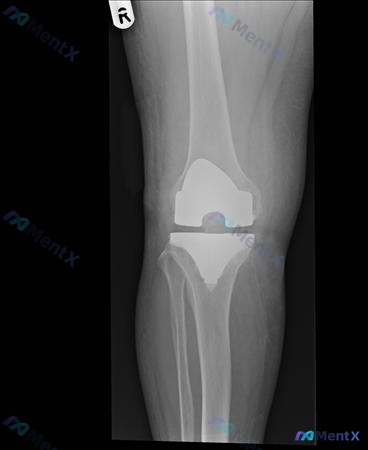

整理了一份右膝全膝关节置换术后的病例资料,感觉下一步的决策挺有代表性的,放出来大家讨论看看。 基本情况 - 58岁男性 - 右膝TKA术后6个月,持续疼痛、僵硬 目前已有的检查结果 1. 实验室:ESR 45mm/hr(0-20),CRP 13.5mg/l(<10) 2. 关节抽吸:WBC 850/...